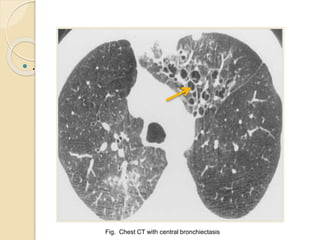

Radiologic Investigations

 HRCT findings

◦ Central bronchiectasis

◦ Mucus plugging with bronchoceles

◦ Consolidation

◦ Centrilobular nodules with tree-in-bud

opacities

◦ Bronchial wall thickening

◦ Areas of atelectasis

◦ Mosaic perfusion with air trapping on

expiration

CHEST 2009; 135:805–826

◦ Fig. CT chest of ABPA patient with Mucoid impaction of

central bronchiectasis and Atelectasis

Fig. Chest CT with central bronchiectasis